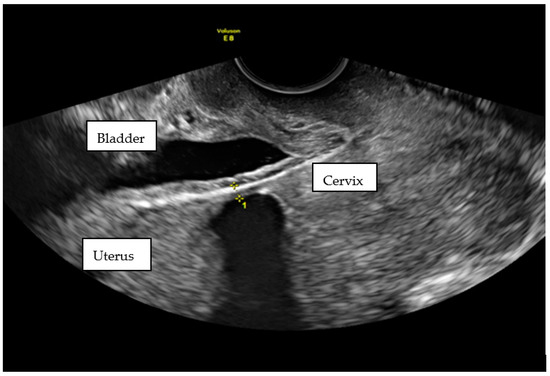

1.1. Case 1

1.2. Case 2